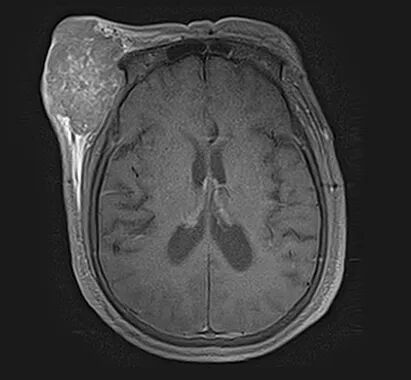

治疗前

治疗前(影像图)